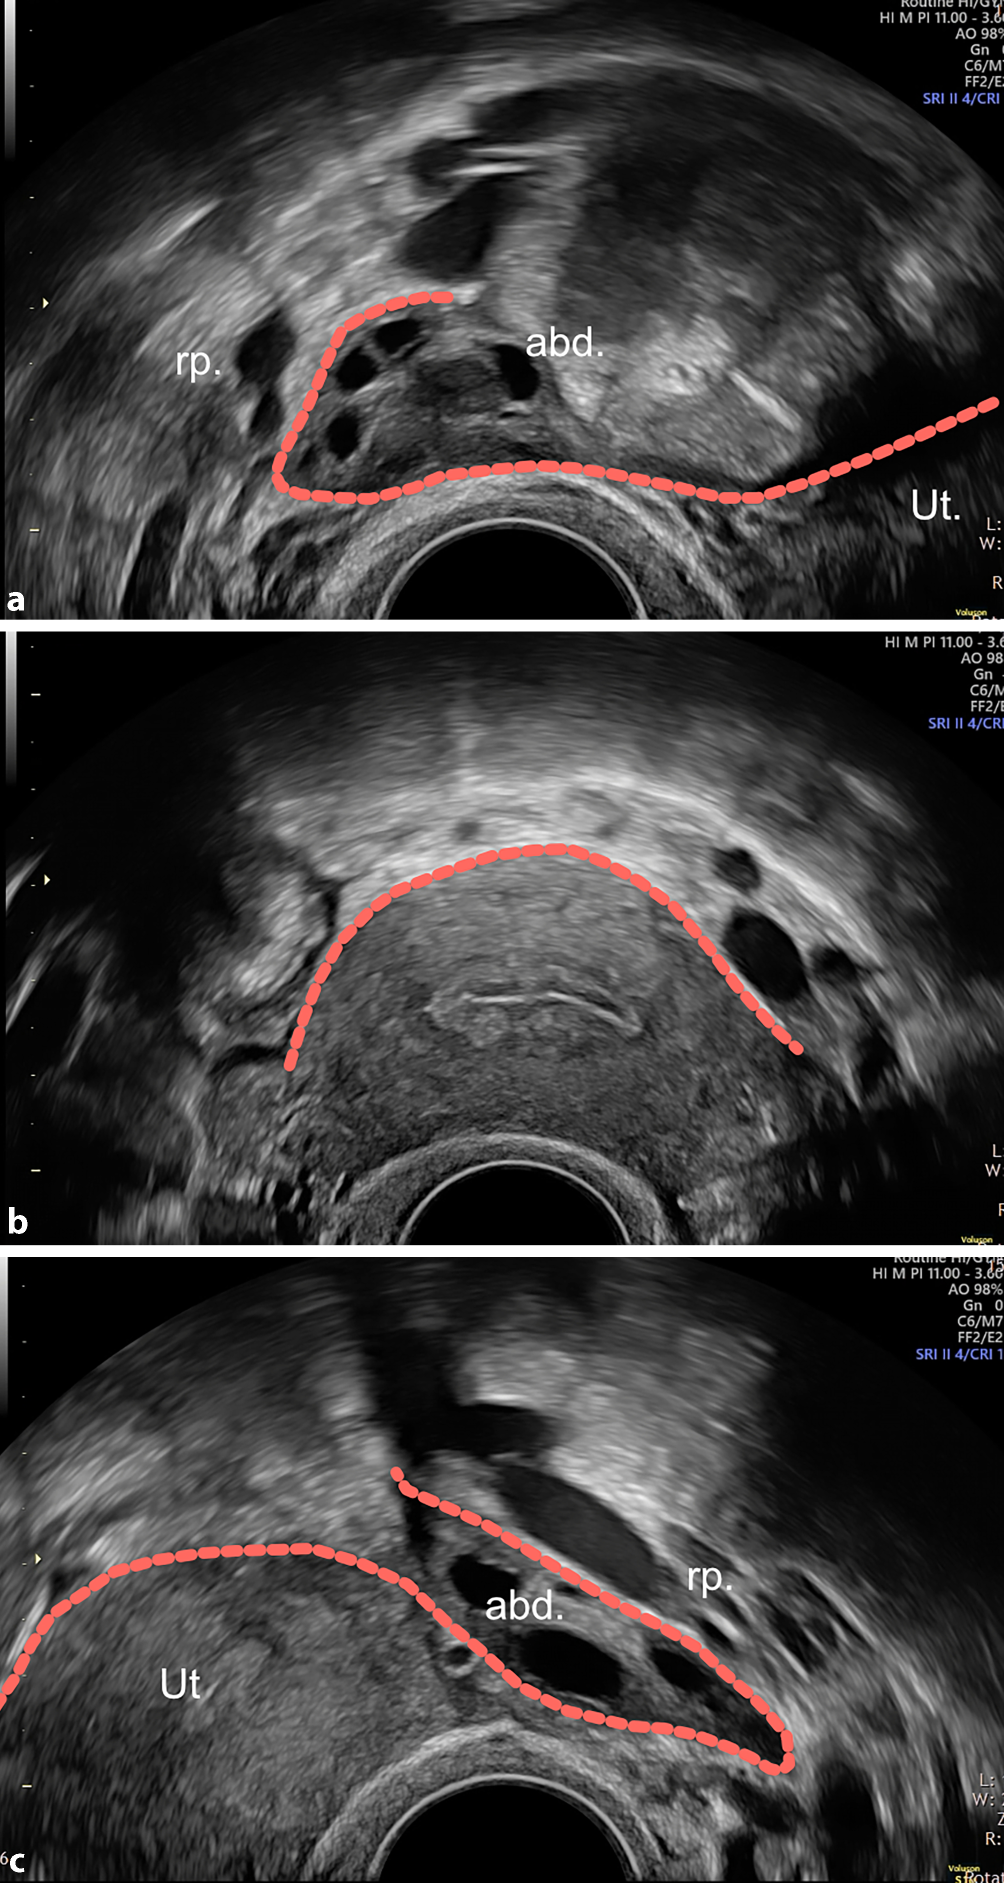

Abb. 3

„Tail“, „tent“ und „omega sign“. Im Querschnitt beschreibt die WSL an der Uterusoberfläche eine Art Igluzelt („tent sign“, b). Die seitlichen Ausläufer schlagen lateral schwänzchenartig nach kranial um (rechts und links „tail sign“, ac). Insgesamt ergibt sich daraus das „omega sign“ (ac), welches eine grossflächige Beurteilung des Peritoneums im kleinen Becken mit einer klaren Darstellung der Beckenwand erlaubt. abd. abdominal, rp. retroperitoneal, Ut. Uterus

Bild vergrößern

Nun kann der Griff der (immer noch um 90 Grad gedrehten) Vaginalsonde etwas nach rechts (respektive links) bewegt werden, um den Bereich links (respektive rechts) der WSL zu beurteilen (laterales Kompartiment). Das „tent sign“ der WSL geht dabei nach lateral nahtlos auf das Peritoneum der Beckenwand über und beschreibt dabei eine schwänzchenartige Kurve nach oben („tail sign“, Abb. 3a, c). Über die gesamte Breite des kleinen Beckens ergibt sich somit die Abfolge „tail-tent-tail“, was aneinandergereiht etwa der Form eines Omegas entspricht („omega sign“, Abb. 3a–c).